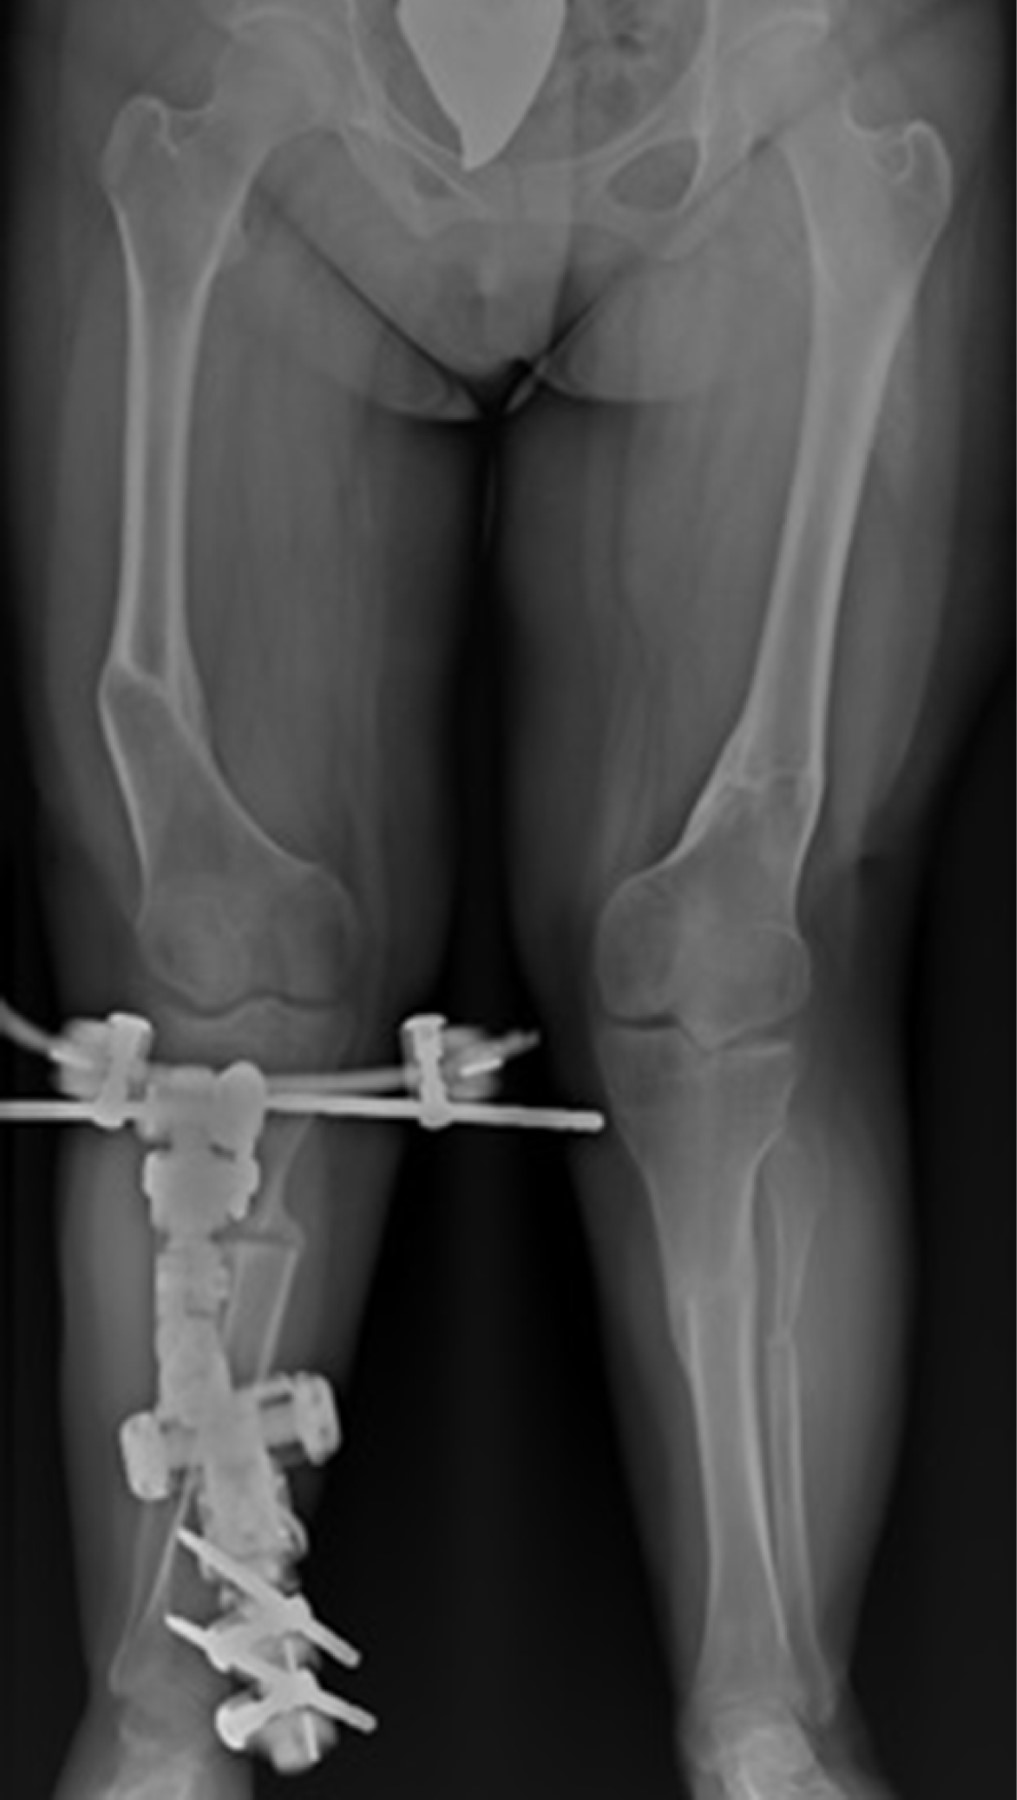

A la edad de 15 años se realizó la última intervención por continuar con deformidad valga en tibia derecha. Por lo que se realizó nuevamente una osteotomía en la tibia derecha y la colocación de fijador externo articulado (Figura 6).

En la actualidad, con edad de 16 años, cuenta con mejoría a la marcha siendo claudicante, no dolorosa. Alineación de miembros pélvicos. Flexión de rodillas a 100 grados de manera bilateral. Con últimas mediciones radiográficas: MAD de 25 mm derecho y 25 mm izquierdo (Figura 7).

Figura 6

Figura 7